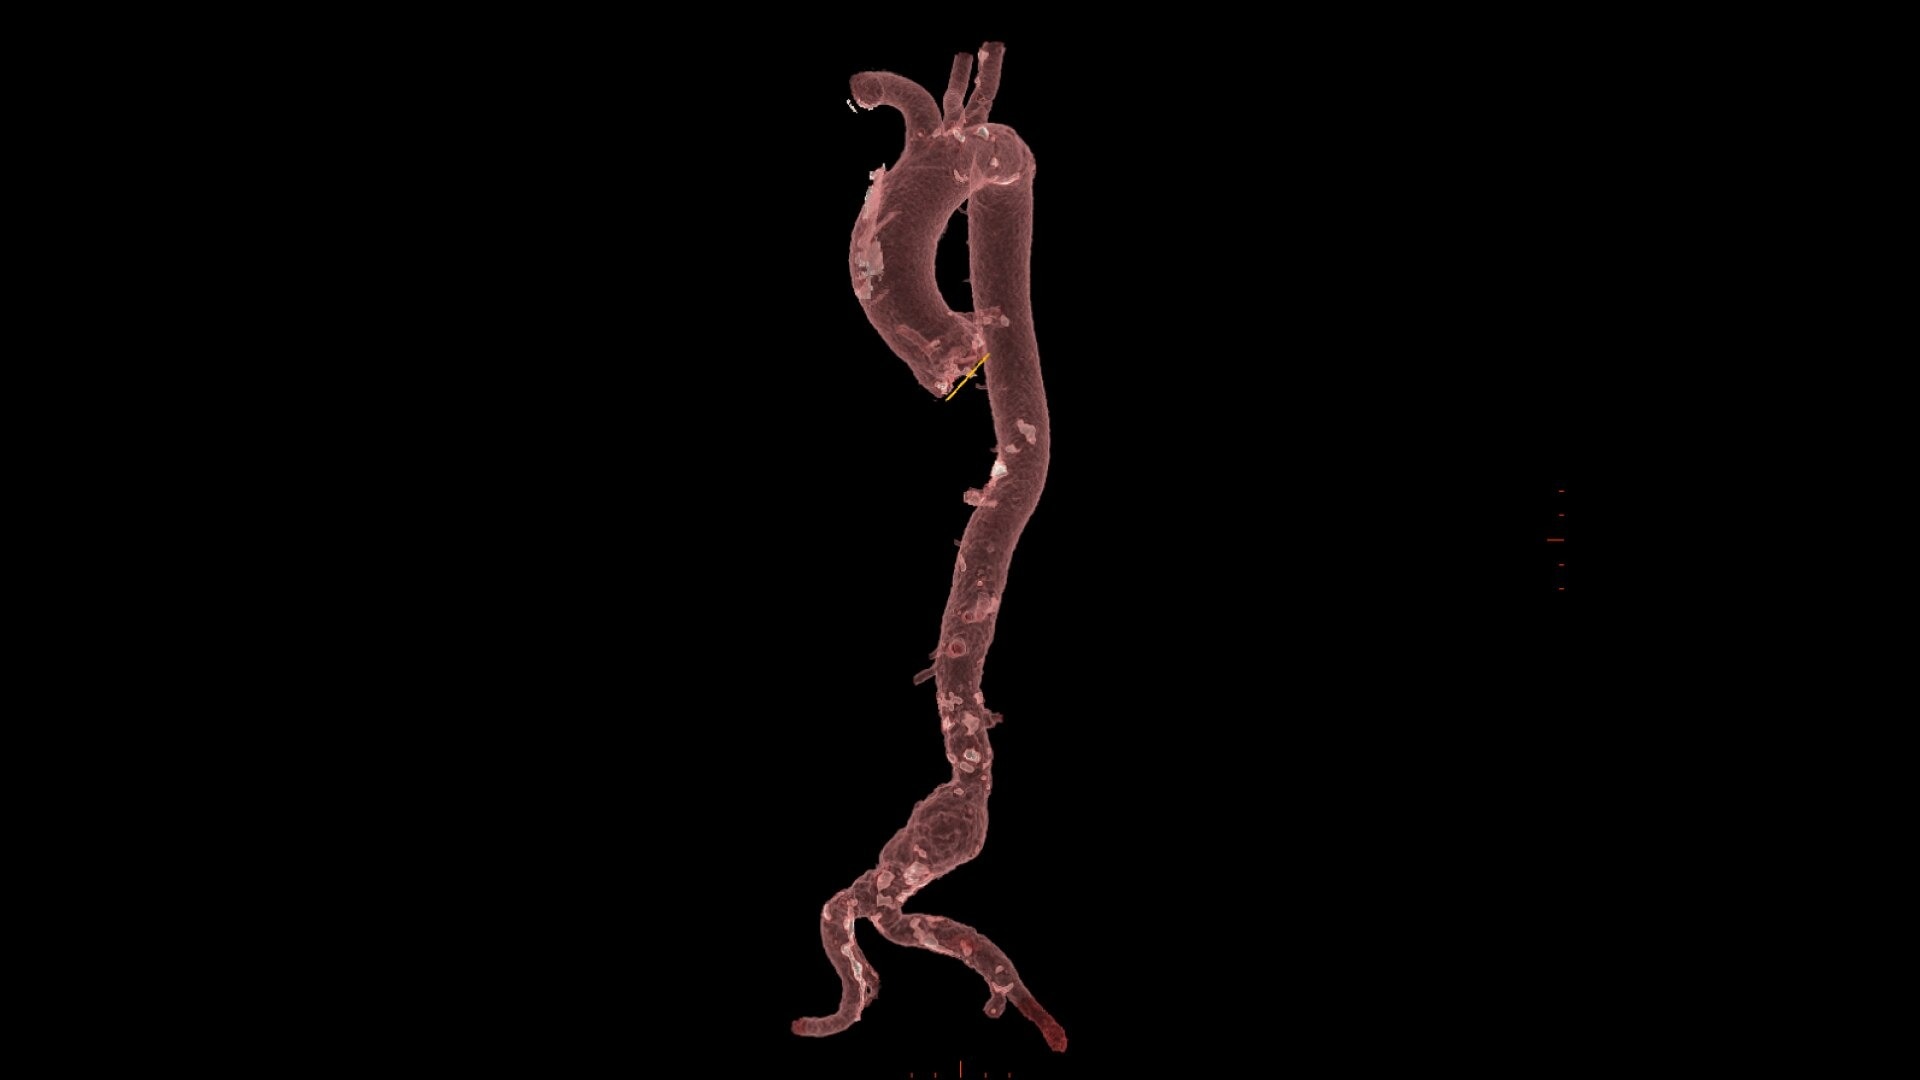

PLAN

0-click aorta segmentation and valve definition makes accurate valve sizing accessible to anyone.